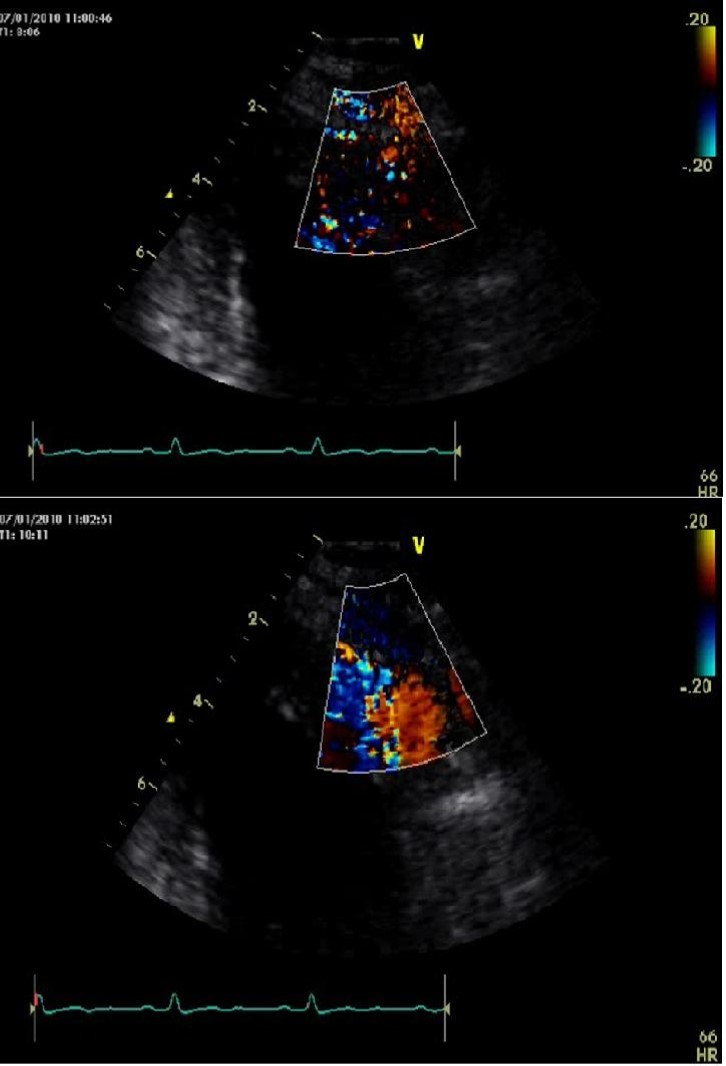

He was asymptomatic, in good general conditions, blood pressure 120/80 mmHg, no murmurs. The electrocardiogram showed sinus bradycardia (55 bpm) and left ventricular hypertrophy signs (deep and symmetric negative T waves in DI, aVL, V2 till V6). Echocardiogram (VIVID 7, 2-4 MHz probe) showed non classical apical hypertrophic cardiomyopathy (Figure 2), localized at anterior, lateral and posterior apex (septum was preserved), with no obliteration of apical cavity. By mean of color-Doppler evaluation, we observed multiple and thin color flows from LAD draining into apical region. Pulse-wave Doppler temporization was exclusively diastolic (Figure 3). Stress echocardiography with accelerate dipyridamole resulted negative for inducible ischemia and no variation in fistula flow was detectable. Inguinal hernia intervention was safely performed and the patient was advised to undergo periodical cardiologic controls.

Figure 3.Echo-color Doppler evalutation of left anterior descending artery fistula draining in left ventricular cavity